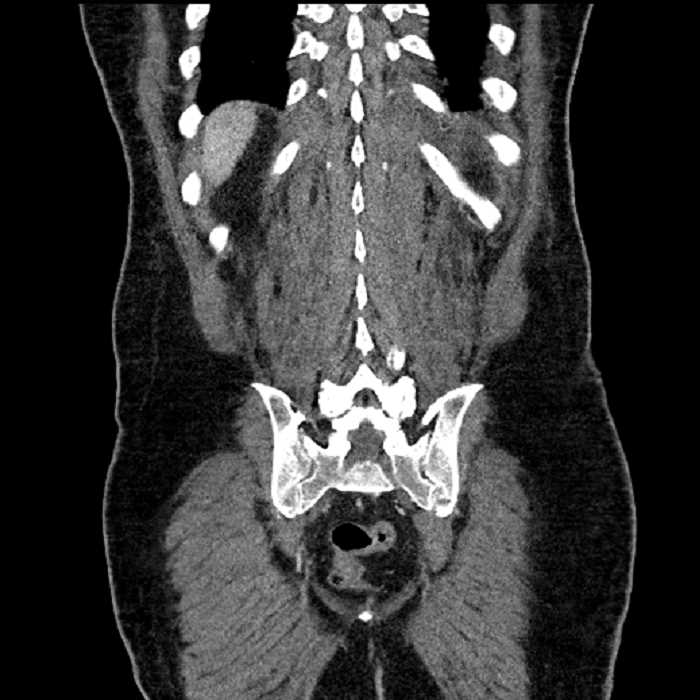

Age: 63

Sex: Male

Indication: Abdominal pain

• High grade stenosis of the left common iliac artery, with the left internal and external iliac arteries remaining patent

• Ankylosis of both sacroiliac joints

• Hepatic abscess

Acute sigmoid diverticulitis complicated by a small contained perforation and a large abscess in the right hepatic lobe. Additional small subcapsular abscesses along the anterior margin of the left hepatic lobe.

High grade stenosis of the left common iliac artery. The left external and internal iliac arteries are patent.

Hepatic abscess showing the double target sign with low density internally surrounded by a thin inner enhancing rim (red arrow) and ill-defined outer low density rim (yellow arrow). Blue arrow indicates an internal septation. Red arrows: additional smaller subcapsular abscesses. Red arrow: focal contained perforation associated with diverticulitis.